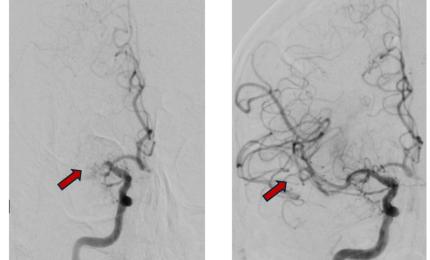

Anh Y.S (42 tuổi, quốc tịch Hàn Quốc) bị đột quỵ và hôn mê sâu suốt 80 ngày, được Bệnh viện FV cứu chữa hồi tỉnh kỳ d